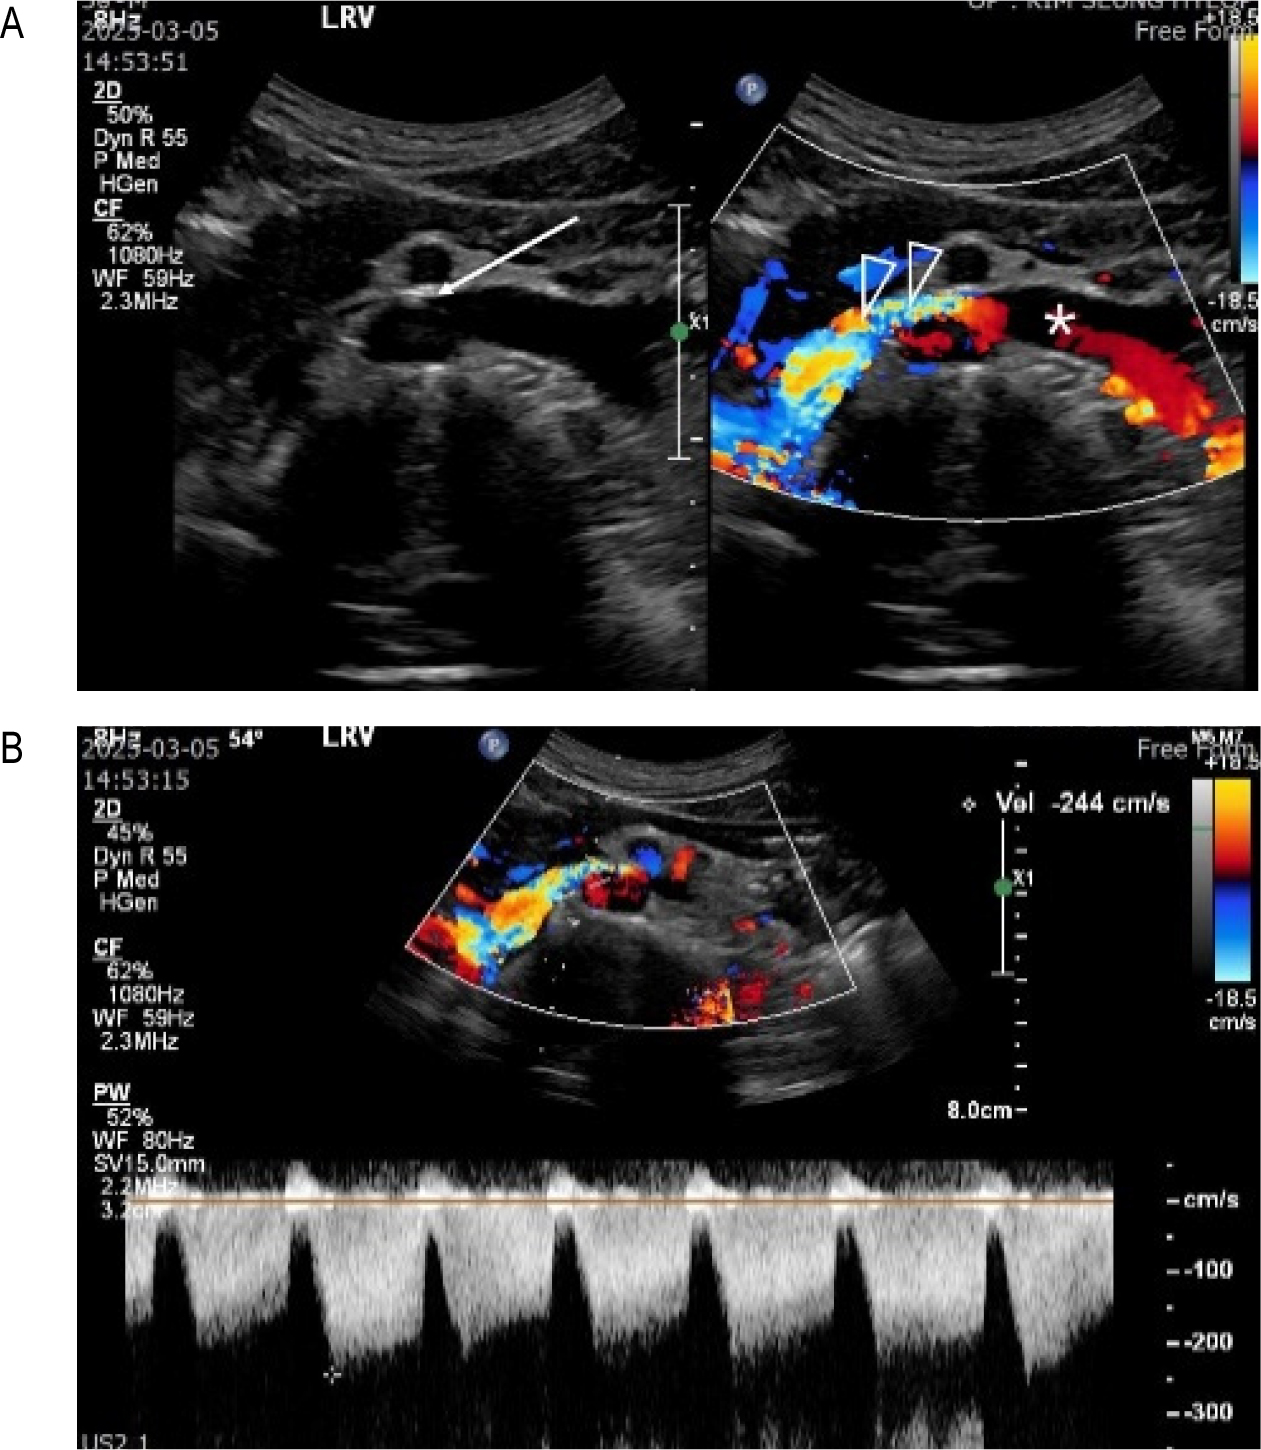

NCS가 의심되는 환자에서 NCP가 있는지를 확인하는 방법은 과거에는 대퇴정맥을 통해서 카테터를 LRV까지 넣고 정맥조영을 하면서 LRV이 눌린 부위 전후의 압력을 측정해서 그 차이가 3mmHg 이상이면 NCP가 있는 것으로 진단했지만 요즘은 이런 침습적인 진단법은 거의 쓰지 않고 도플러초음파나 CT로 진단한다. 왼쪽 콩팥으로부터 나오는 H-LRV의 정상혈류속도는 10-20 cm/sec 정도이고 AM-LRV 부위는 정상인에서도 약간 눌리기 때문에 H-LRV의 혈류속도보다 좀 높아서 40-50 cm/sec 정도이다. AM-LRV의 혈류속도가 정상의 2배, 즉 80-100 cm/sec 이상이면 NCP를 의심할 수 있고 도플러초음파 진단은 AM-LRV의 최고혈류속도가 100 cm/sec 이상일 때를 기준으로 한다.

혈뇨가 있는 사람에서는 초음파검사보다 CT를 먼저 하는 경우가 흔하다. 조영증강 CT (Contrast-enhanced CT, CECT)의 초기영상에서 왼쪽 콩팥으로부터 나온 조영증강된 LRV이 진하게 보여서 혈관이 눌리는 소견과 함께 LRV 혈류가 대정맥으로 이동하는 모습이 잘 보이는데 이 모양으로 NCP를 진단할 수 있다. AM-LRV이 많이 눌려서 혈류 속도가 빨라지면 진하게 조영 된 LRV의 혈류가 조영이 덜된 대정맥 안으로 뿜어져 들어가는 소견을 보이면 NCP를 의심할 수 있고 [그림 1], 도플러 초음파검사를 해서 혈류속도가 100 cm/sec 이상인 것을 확인하면 NCP 가 있다고 진단하며 [그림 2], 이 환자가 NCP에 의한 증상을 가진 환자라면 NCS로 진단하게 된다.